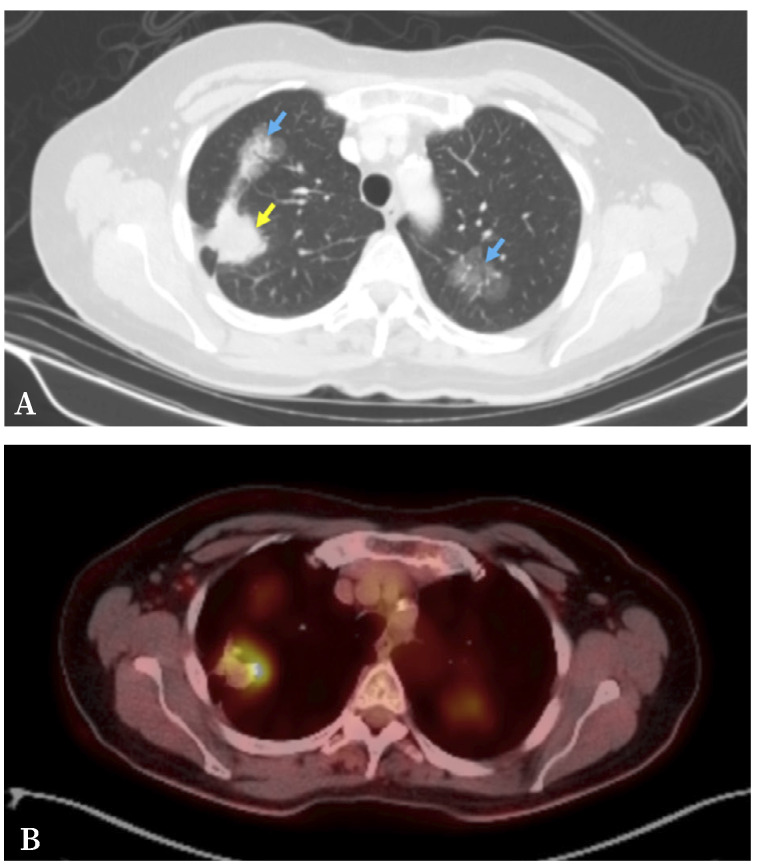

Multiple primary lung cancer can be synchronous or metachronous based on the timing of lesion onset. Despite the existing classification criteria for lung cancer with multiple lung involvement, it is sometimes challenging to distinguish between lung cancer with multiple lung involvement and intrapulmonary metastases. Moreover, differentiating synchronous multiple primary lung cancer from multifocal ground-glass/lepidic-pattern lung cancer is crucial. While histologic evaluation can aid in diagnosis, molecular analyses are often necessary. We present the case of a female patient diagnosed with triple synchronous primary lung adenocarcinomas. Although the lesions shared the same histological subtype, they exhibited distinct histological patterns and molecular profiles. In cases of lung cancer with multiple lung involvement, it is essential to perform a detailed pathological study for an accurate diagnosis and appropriate therapeutic interventions.